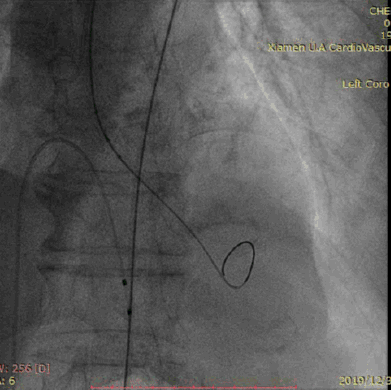

冠脉造影提示:右冠优势型,三支血管病变,LAD中段狭窄60%,D1近段狭窄80%,LCX远段狭窄90% ,RCA中段50%。TIMI血流3级,未见闭塞血管。

直头导丝跨瓣